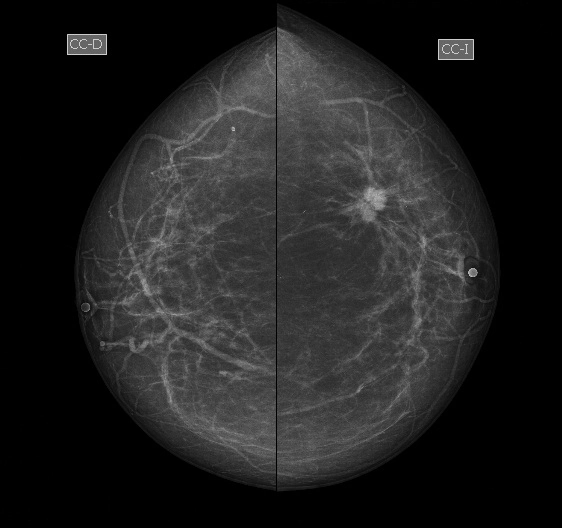

Phân loại Bi-RADS

Phân loại BI-RADS (Breast Imaging Reporting and Data System- BI-RADS)